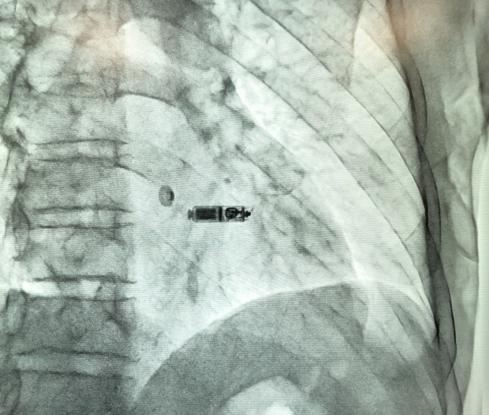

这次为患者植入的Micra无导线起搏器又称“胶囊起搏器”,是当今全球体重最轻、体积最小的起搏器,仅重2克,花生米大小的胶囊内却整合了当今世界最先进的起搏技术元件。植入时,“胶囊起搏器”犹如被线牵住的电子小“风筝”,在通过血管送到患者右心室着床后,小“风筝”放飞并独立完成传统起搏器的各项工作。无导线起搏器避免了传统起搏器植入带来的“皮肉之苦”,也减少了因起搏器皮囊可能感染而带来的烦恼,这一革命性的起搏技术问世之初就给全球起搏领域带来了巨大的振奋和影响,其临床试验结果于2016年2月发表在国际顶级医学期刊《新英格兰医学杂志》。周胜华教授团队高度敏锐洞悉无导线起搏器临床应用的巨大潜能及可能面临的问题并大胆提出学术观点,提出了无导线起搏器的下一步改进方向,和国际上的主流学术观点不谋而合,《新英格兰医学杂志》于同年第一时间迅速刊发了团队的学术观点,在国内外引起强烈反响和共鸣。

获悉Micra起搏器在我国正式上市的消息后,周胜华教授团队立即通知了一位适合植入无导线起搏器的患者黄先生。黄先生于2018年第一次植入起搏器,后因对起搏器金属壳产生过敏排异而先后3次常规植入传统起搏器,最终都因排斥反应导致囊袋感染破溃将起搏器取出。没有起搏器保护的黄先生随时面临心脏停跳带来的生命危险,这款“黑科技”无导线起搏器成为黄先生的救命“及时雨”。

为了保证手术安全和顺利进行,医院专门安排了心内科副主任、湖南省心电生理和起搏专业委员会主任委员刘启明教授“主刀”,在李旭平、刘振江、吴智鸿等科室骨干力量的密切配合下,仅用时40分钟就完成了当今世界起搏领域最神奇又振奋人心的手术。专程前来做工程技术指导的美方专家、美敦力公司首席工程师Dan Flynn先生对团队过硬的心电生理技术赞不绝口。